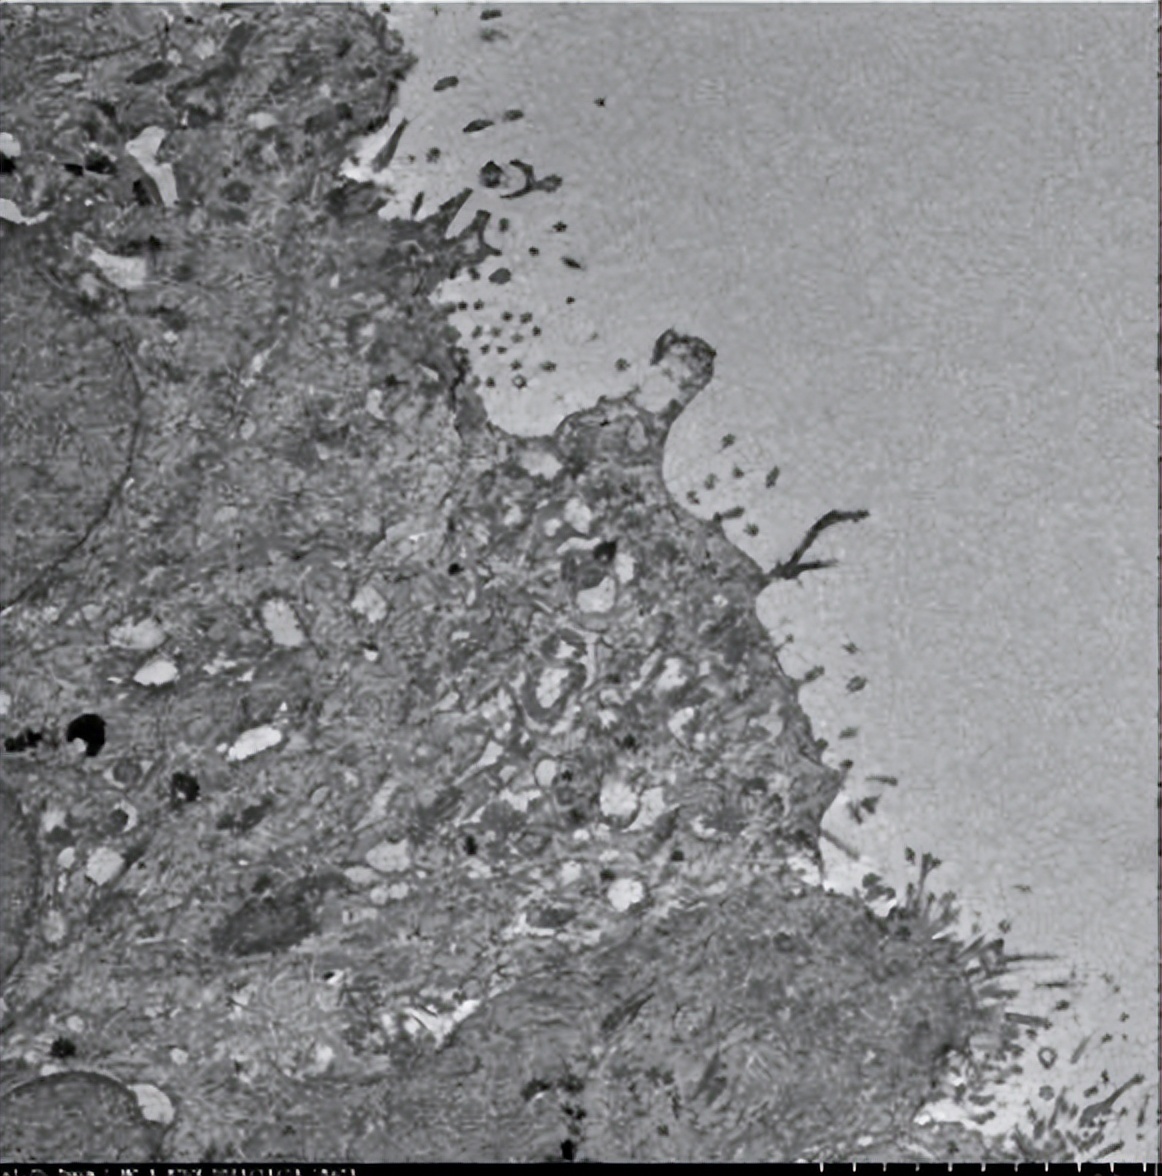

电镜(图3):部分上皮细胞纤毛少,有纤毛缺失、短小,未见动力臂(放大1000倍)。

图3.电镜示部分上皮细胞纤毛少,有纤毛缺失、短小,未见动力臂(放大1000倍)

3、辅助检查:①实验室检查:WBC、N%轻度升高,CRP、真菌D-葡聚糖、内毒素试验阴性;②抗酸染色和T-SPOT阴性;③胸部CT:支气管扩张合并感染,可见「树芽征」,左下肺可见粟粒样结节;鼻窦CT:双侧筛窦、上颌窦可见黏膜增厚、水肿,未见骨质破坏,右侧筛窦较左侧病变重;④支气管镜活检组织电镜:部分上皮细胞纤毛少,有纤毛缺失、短小,未见动力臂(放大1000倍)。

我们根据纤支镜活检组织电镜下呈现纤毛短小、动力臂消失的特点,拟诊为PCD,这也符合患者反复咳痰的临床表现。为了进一步验证,我们通过全外显子测序,尝试是否可以检测出某种致病基因。经测序,患者携带有CCNO致病基因c.303C>A杂合变异以及c.248_252dup杂合变异。最终,我们诊断为原发性纤毛运动障碍。

3、辅助检查:①胸部CT:支气管扩张合并感染,有典型的「树芽征」,并且在左下肺可见粟粒样结节;②鼻窦CT:双侧筛窦、上颌窦可见黏膜增厚、水肿,未见骨质破坏,右侧筛窦较左侧病变重;③支气管镜活检物电镜:部分上皮细胞纤毛少,有纤毛缺失、短小,未见动力臂(放大1000倍);④全外基因检测:CCNO基因c.303C>A杂合变异以及c.248_252dup杂合变异,根据ACMG致病性证据,该变异为无功能(LOF)变异,可能导致翻译产生的蛋白截断或降解。